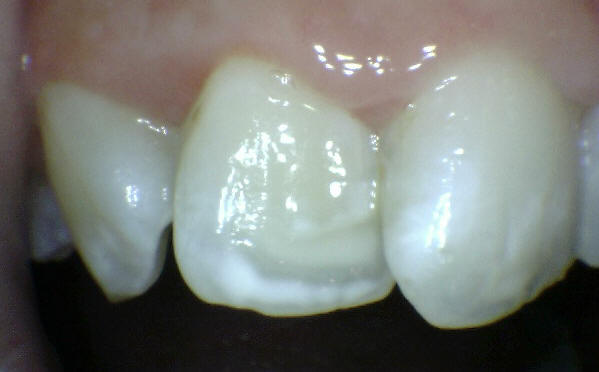

1 Opacidad del esmalte: Cambio de color del blanco al crema

• Diagnóstico diferencial con fluorosis. Las fluorosis leve suele mostrar estas características.